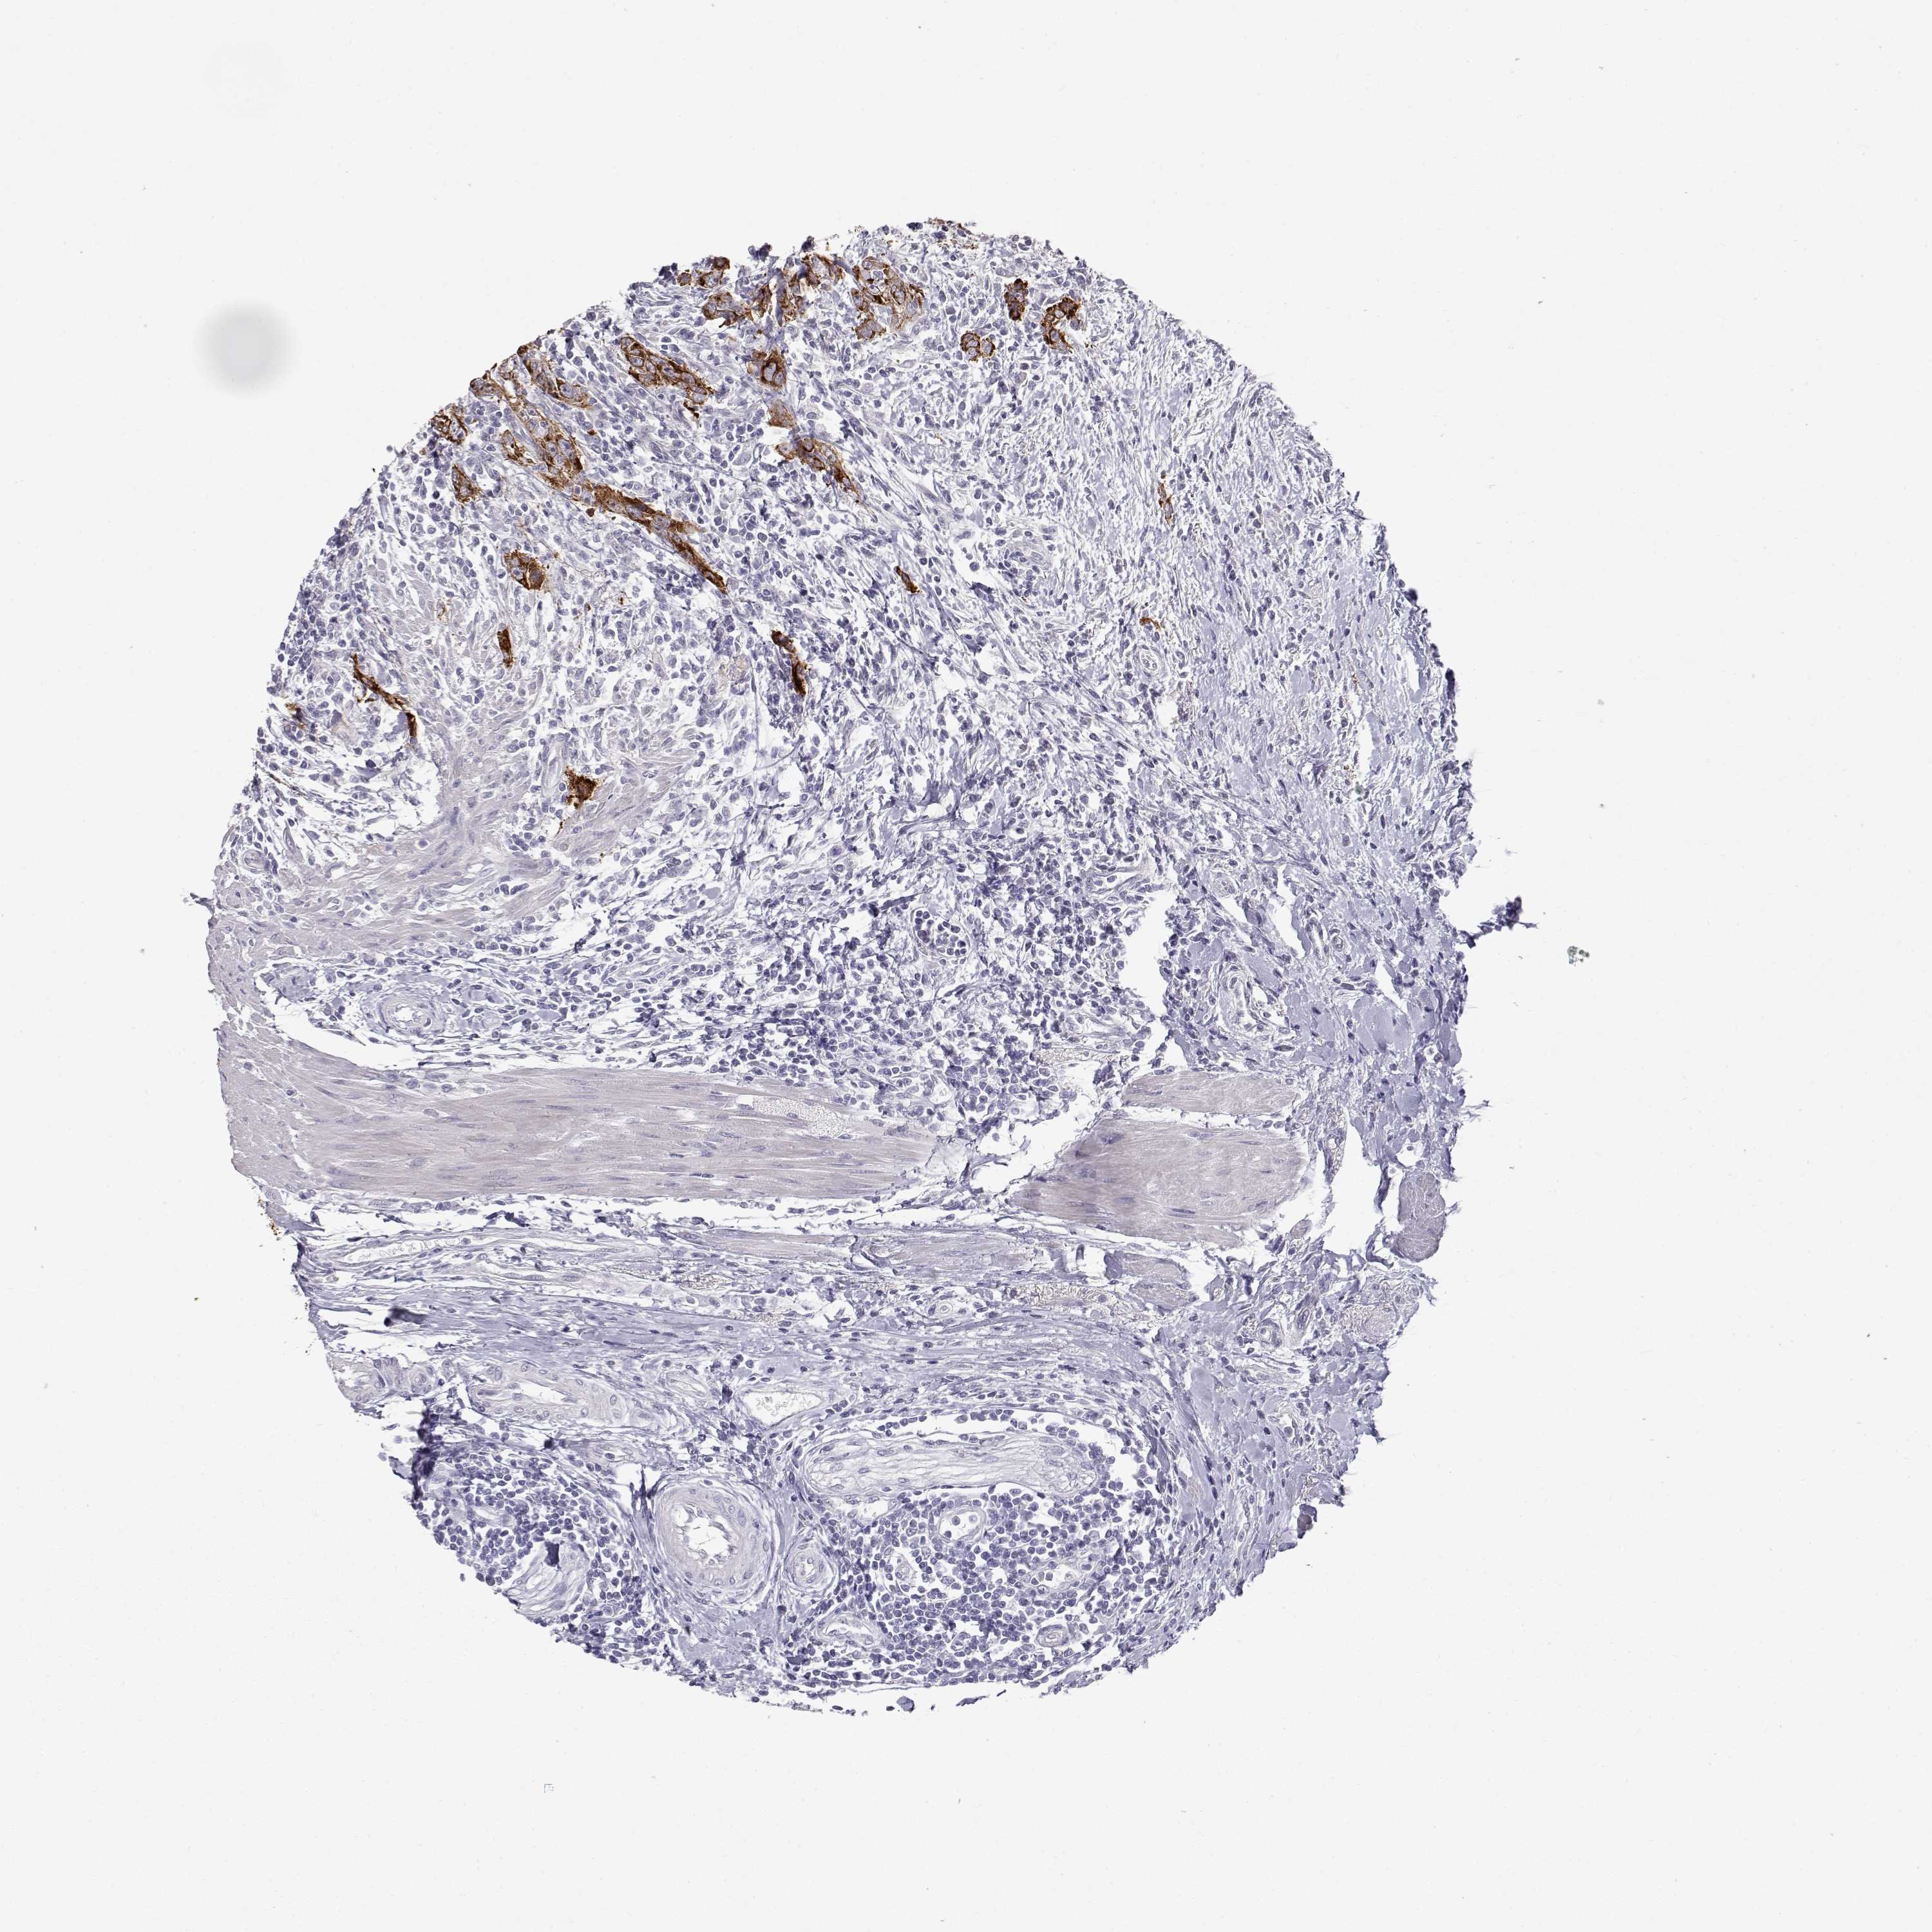

UROTHELIAL CANCER - Protein expressioni

A mouse-over function shows sample information and annotation data. Click on an image to view it in a full screen mode. Samples can be filtered based on level of antibody staining by selecting one or several of the following categories: high, medium, low and not detected. The assay and annotation is described here.

Antibody stainingi

Antibody staining in the annotated cell types in the current human tissue is reported as not detected, low, medium, or high, based on conventional immunohistochemistry profiling in selected tissues. This score is based on the combination of the staining intensity and fraction of stained cells.

Each image is clickable and will lead to virtual microscopy that enables deeper exploration of all samples and also displays staining intensity scores, fraction scores and subcellular localization as well as patient and tissue information for each sample.

Antibody HPA008069

Antibody CAB078183

Urothelial carcinoma, Low grade

Urothelial carcinoma, High grade

Urothelial carcinoma, NOS